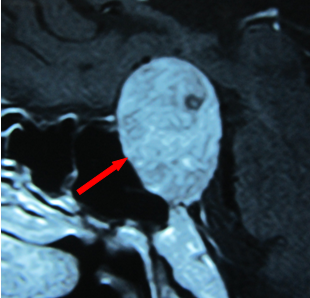

紅箭頭示垂體瘤